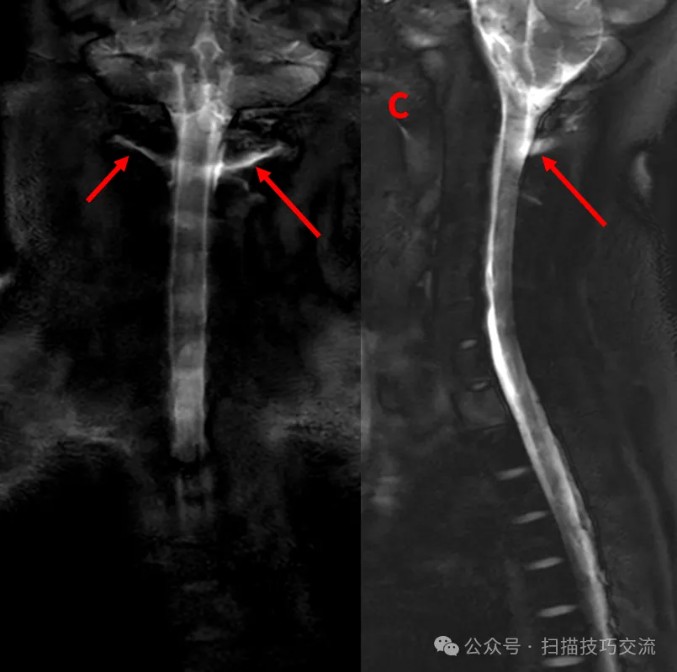

来都来了,再加个3D MRM看一下,